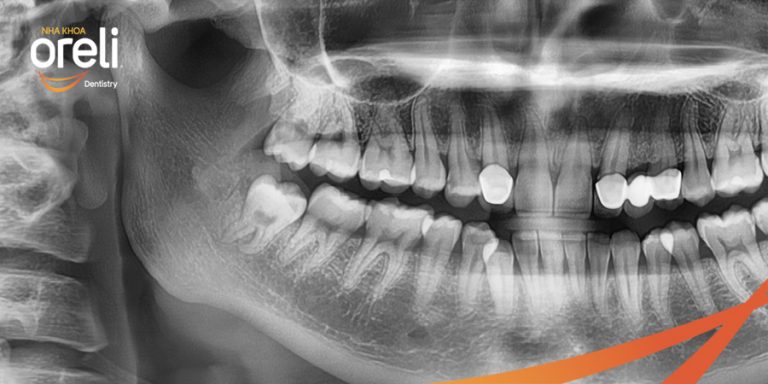

Nhổ răng khôn hàm dưới mọc lệch – Ca thực tế tại Oreli Buôn Ma Thuột

Nhổ răng khôn

Mọc lệch